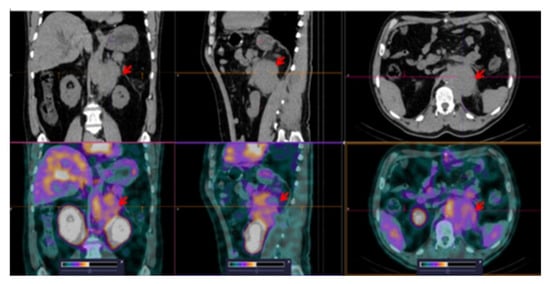

3.3. [99mTc]Tc-TG SPECT/CT Imaging of Nodal and Extranodal Lesions